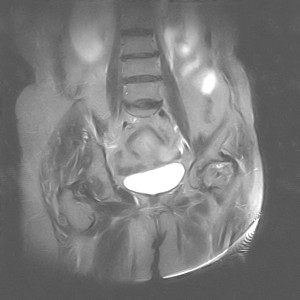

图像太差了 1、右侧臀肌旁脓肿? 建议增强 2、左侧股骨头坏死并半脱位

1、左侧股骨头坏死并髋关节半脱位;

2、右侧臀肌感染,(可能褥疮所致)